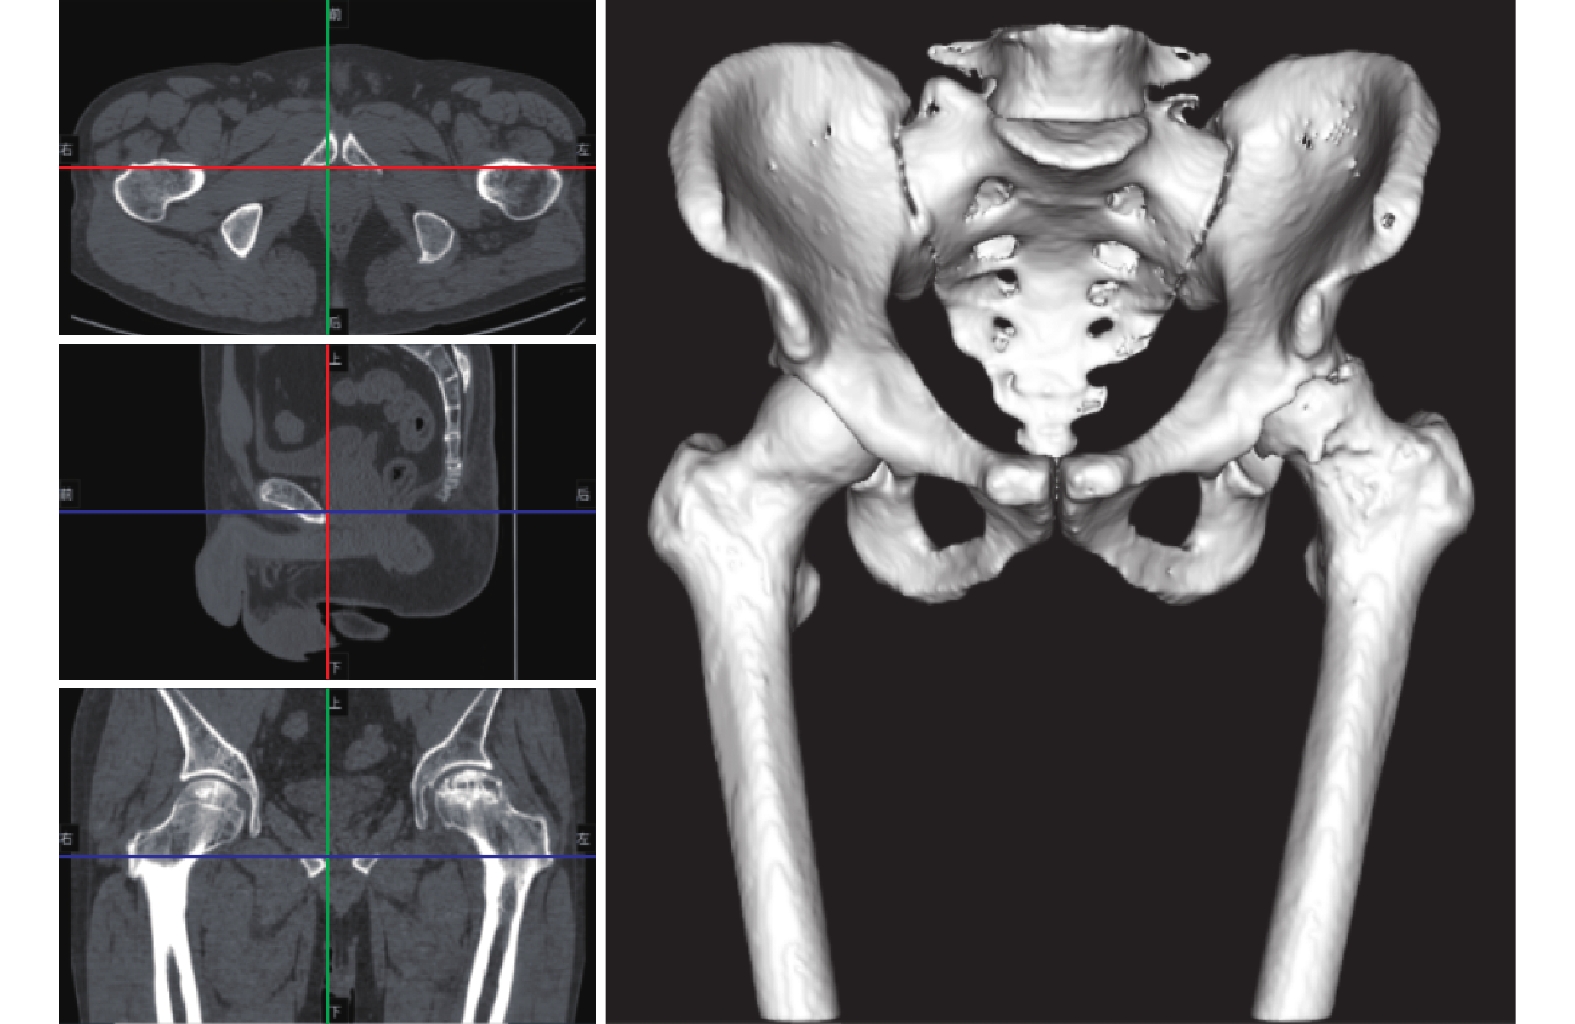

導入界面如圖3 所示,分別顯示三軸聯動與三維重建顯像。軟件使用算法自動去除雜質影響,精確顯示骨質,精確實現 3 個窗口的三軸聯動。